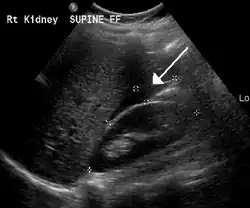

A small amount of anechogenic-free fluid in the recto-uterine pouch is commonly found in both intrauterine and ectopic pregnancies.[5] The presence of echogenic fluid is estimated at between 28 and 56% of women with an ectopic pregnancy, and strongly indicates the presence of hemoperitoneum.[5] However, it does not necessarily result from tubal rupture but is commonly a result from leakage from the distal tubal opening.[5] As a rule of thumb, the finding of free fluid is significant if it reaches the fundus or is present in the vesico-uterine pouch.[5] A further marker of serious intra-abdominal bleeding is the presence of fluid in the hepatorenal recess of the subhepatic space.[5]